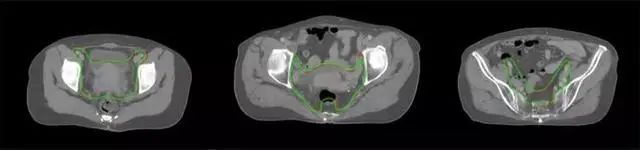

四、放射治療智能勾畫軟件

放射治療,簡(jiǎn)稱放療,是治療腫瘤主要手段之一,利用放射線破壞照射區(qū)(靶區(qū))的細(xì)胞,使腫瘤細(xì)胞停止分裂直至死亡,醫(yī)生通常把放射治療形象的比喻為“打靶”,放療前精準(zhǔn)勾畫腫瘤靶區(qū)范圍是腫瘤放射治療的關(guān)鍵步驟。傳統(tǒng)的靶區(qū)勾畫醫(yī)生會(huì)根據(jù)患者多張CT、MRI影像片憑借經(jīng)驗(yàn)進(jìn)行,比較耗時(shí),治療的病人數(shù)量也有限,且靶區(qū)勾畫缺少行業(yè)統(tǒng)一的規(guī)范和標(biāo)準(zhǔn),無法達(dá)到同質(zhì)化,勾畫精確度不理想。

技術(shù)原理

基于深度學(xué)習(xí)人工智能的放療靶區(qū)智能勾畫技術(shù)和自動(dòng)計(jì)劃技術(shù),基于全面的市場(chǎng)調(diào)研和臨床專業(yè)意見,采用獨(dú)創(chuàng)的基于小樣本量的人工智能算法,實(shí)現(xiàn)放療靶區(qū)和危及器官的快速全自動(dòng)勾畫。

產(chǎn)品優(yōu)勢(shì)

縮短至幾分鐘內(nèi)便可完成,大幅提升了放療效率,且人工智能平臺(tái)完成的靶區(qū)勾畫可基本滿足臨床醫(yī)生需求,專家只需審核時(shí)細(xì)微調(diào)整,可顯著提高靶區(qū)勾畫的規(guī)范化及精準(zhǔn)度,讓放療智能化,標(biāo)準(zhǔn)化??筛采w食管癌、鼻咽癌、直腸癌、宮頸癌、肺癌等多種病種。